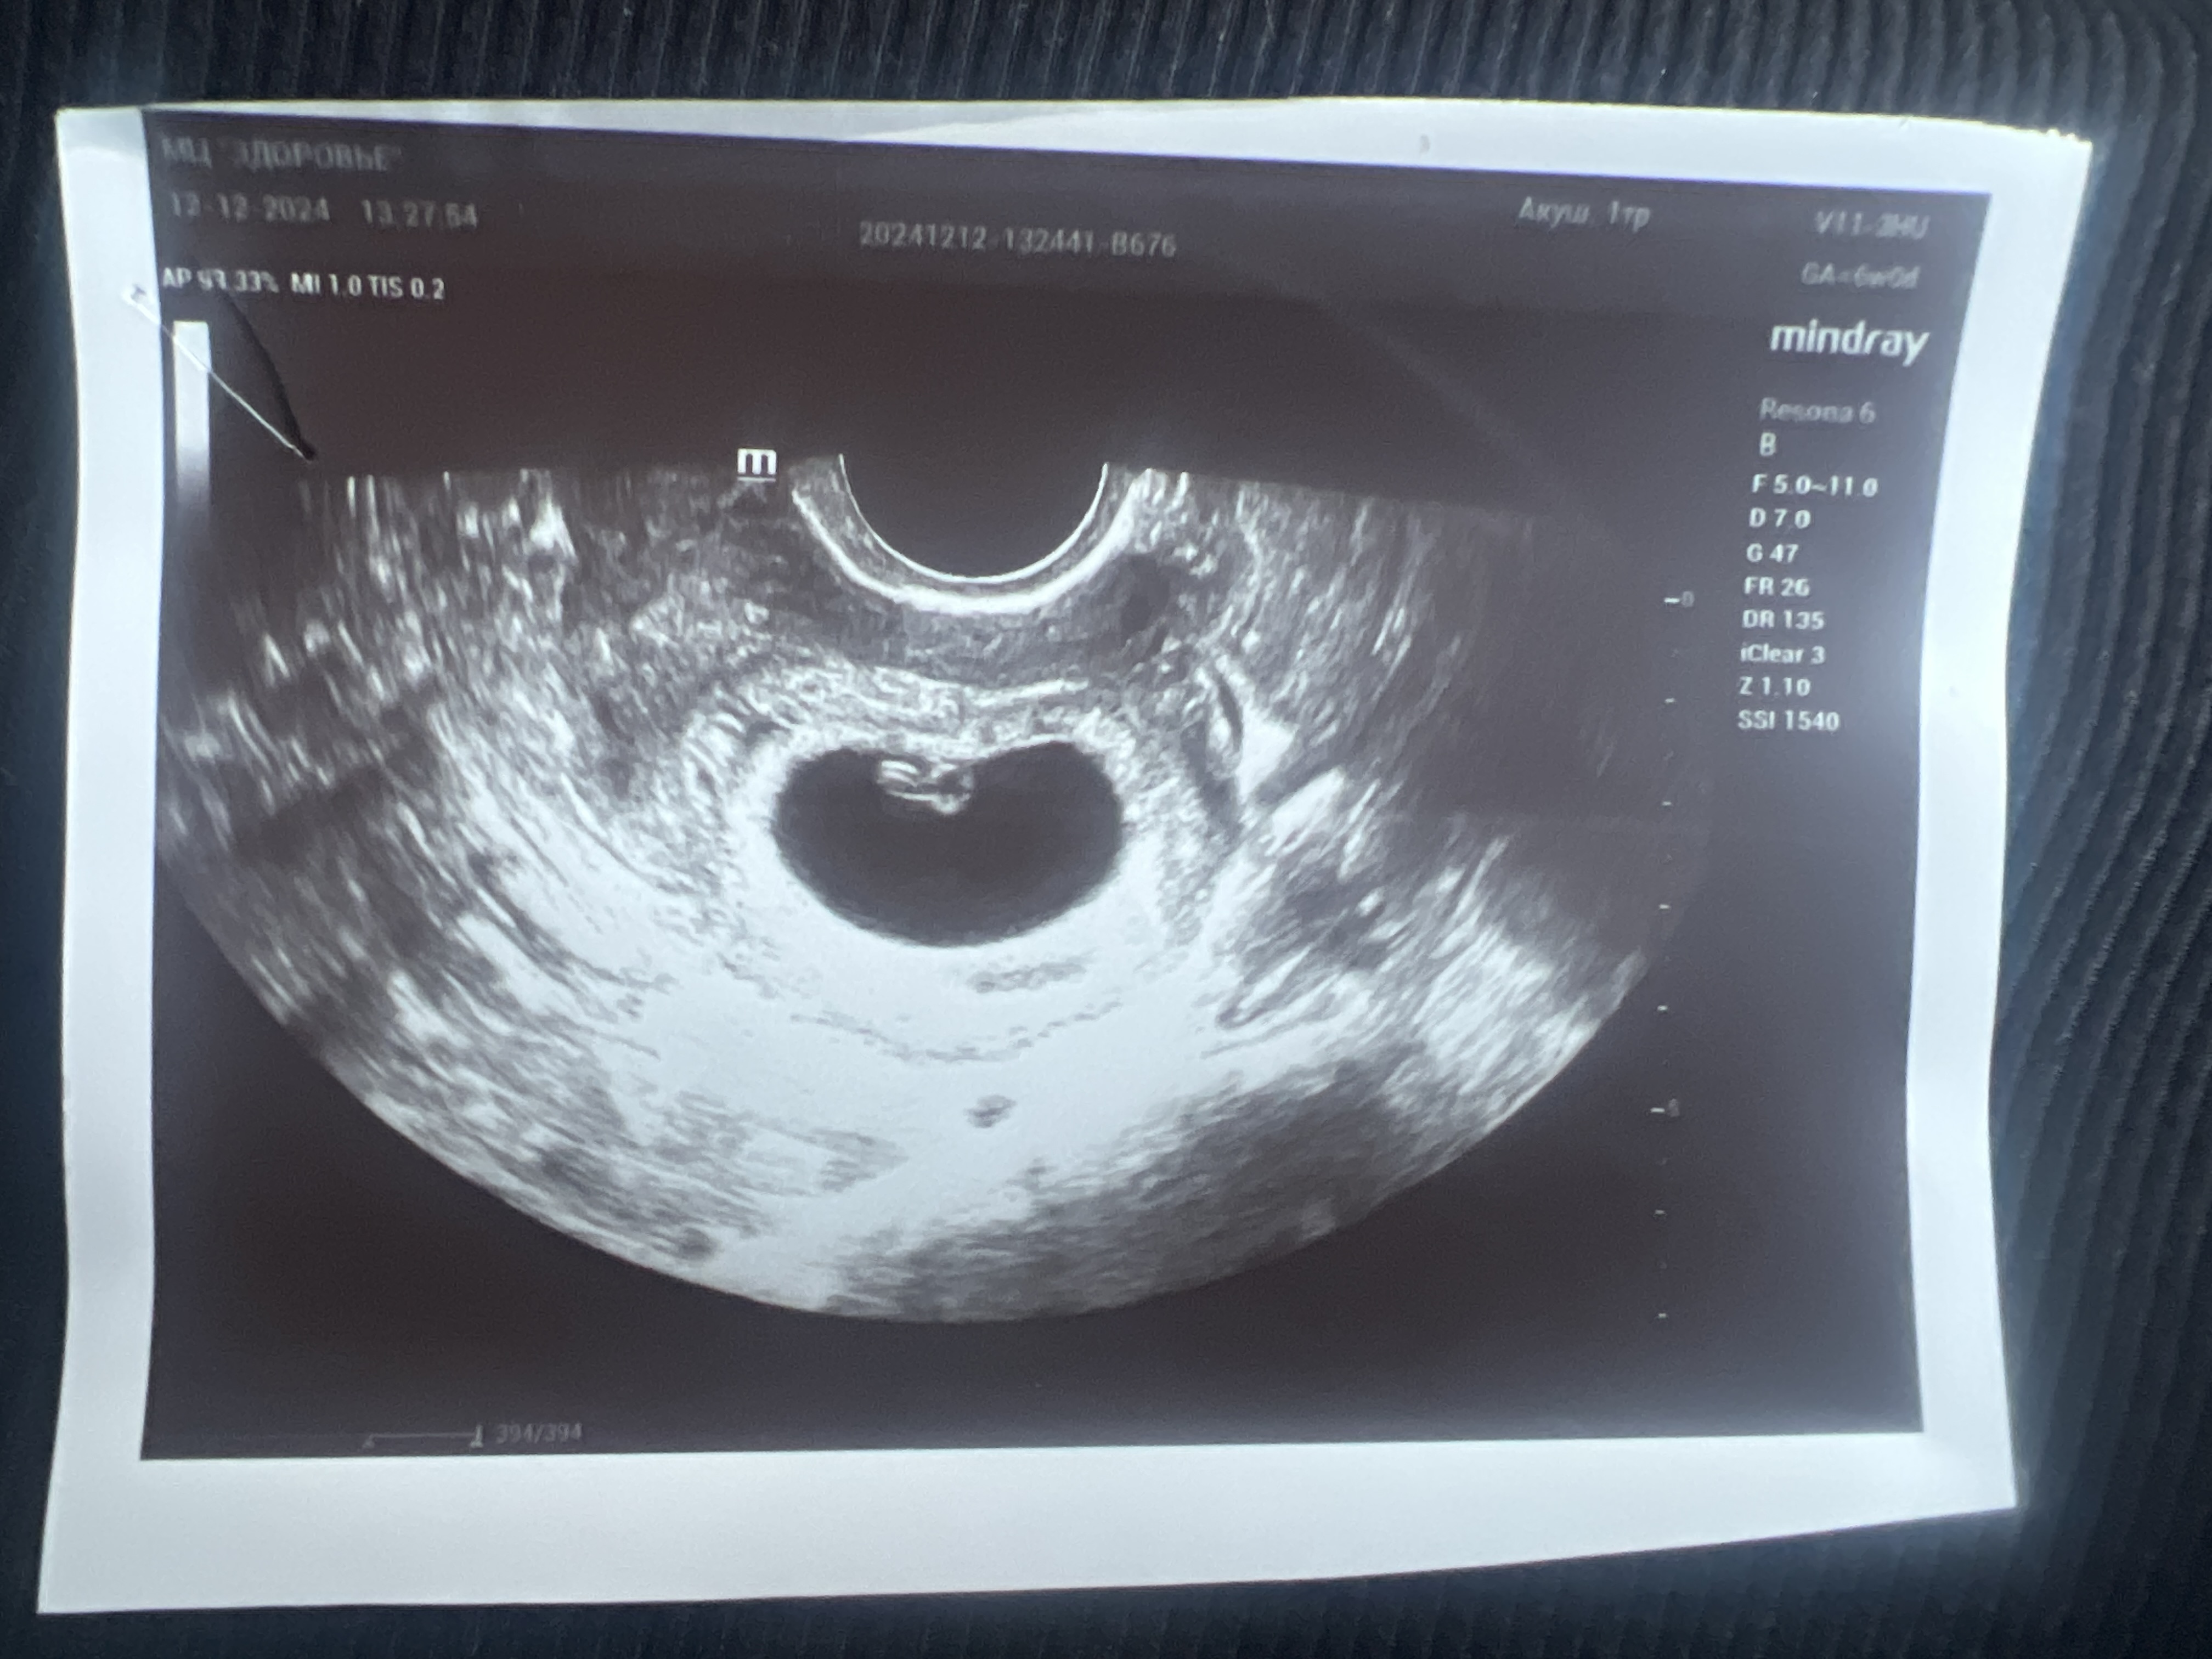

Кто разбирается в методе Рамзи? Трансвагинальное узи, не пойму с какой стороны прикреплена плацента, с правой или левой